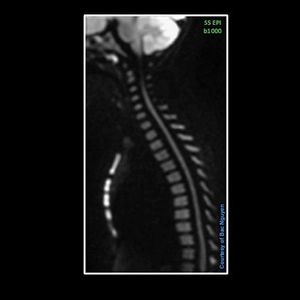

RESOLVE vs. SS-EPI – Spine Imaging @ Siemens 1.5T Aera I must admit, i’m not fully happy with RESOLVE for spine imaging. Due to the time you put into the scan, the results can vary between good, ok and suboptimal. I find it hard to optimize a good and robust RESOLVE for spine, so I’m going back to the old school SS-EPI for further optimizing. With RESOLVE I also notice b value above b600 can give problems due to image quality, if you don’t put extra scantime into it. In this test the SS-EPI had b0, b1000 and ADC map. The resolution is not near as RESOLVE, but the image quality due to high b value, distortion and scantime of only 1min and 40 sec, I must admit I’m surprised. This is just my experience, so if anyone have good experience with RESOLVE for spine imaging, I would like to hear.#s_mri #siemens#mri #dwi